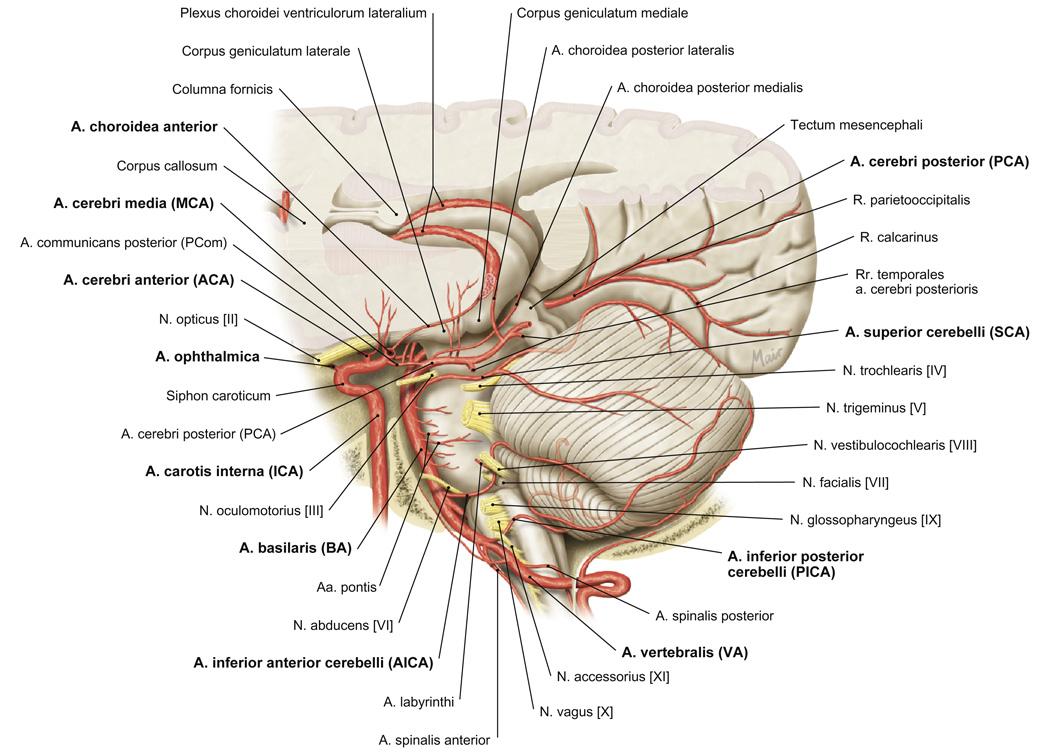

cirkel van Willis

details: zie neuro a vertebralis > a basilaris > a cerebri posterior a carotis interna > a cerebri media a carotis interna > a cerebri anterior a carotis interna > a communicans posterior a communicans anterior